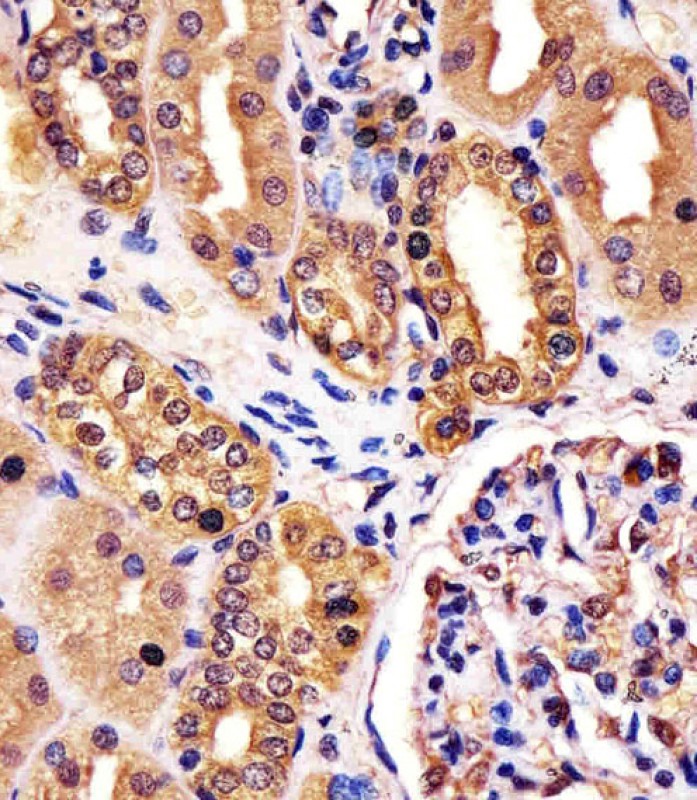

| IHC | 1/100-1/500 | Human,Mouse,Rat |

The RNF7 (N-term) antibody is designed to target the N-terminal region of RNF7 (Ring Finger Protein 7), a component of the E3 ubiquitin ligase complex. RNF7. also known as SAG (Sensitive to Apoptosis Gene), plays a critical role in the ubiquitin-proteasome system by facilitating substrate recognition and polyubiquitination, marking proteins for degradation. It is involved in diverse cellular processes, including oxidative stress response, DNA damage repair, and apoptosis regulation. RNF7 interacts with Cullin family proteins to form functional E3 ligase complexes, such as CRL5 (Cullin-RING ligase 5), influencing pathways like NF-κB signaling and tumorigenesis.

This antibody is commonly used in research applications like Western blotting, immunoprecipitation, and immunofluorescence to detect endogenous RNF7 expression in cell lysates or tissues. Its specificity for the N-terminal region ensures recognition of full-length RNF7. distinguishing it from potential degradation products or splice variants. Validation typically includes testing in knockout cell lines or siRNA-mediated knockdown to confirm minimal cross-reactivity. Dysregulation of RNF7 has been implicated in cancers, neurodegenerative diseases, and oxidative stress-related pathologies, making this antibody a valuable tool for studying disease mechanisms, protein turnover, and post-translational modification pathways. Researchers also employ it to explore RNF7's role in cellular responses to environmental stressors or chemotherapeutic agents.